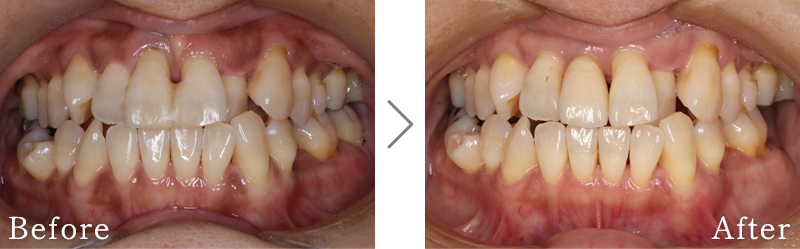

CASE3

主訴 入れ歯も合わず、しっかりと噛んで食事ができないとのことで来院されました。

治療法 上下ともにALL-ON-6と呼ばれる最少本数のインプラントで全ての歯を回復する治療を行なっています。歯の部分は全てセラミックで作成されています。

治療期間 10ヶ月

※矯正治療の期間は含まれておりません。